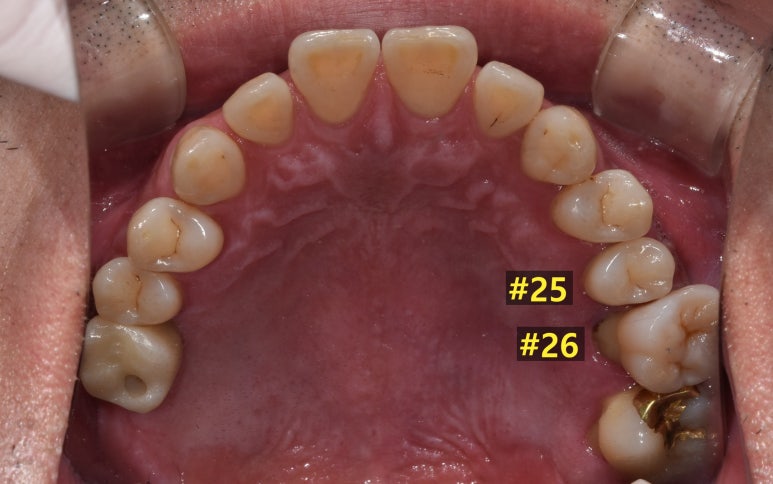

환자분의 첫 내원 시 사진입니다.

우선 살펴보면 임플란트가 필요한 치아는 왼쪽 위 어금니 2개였는데요.

옆에 있는 #26 치아는 염증이 심해 잇몸뼈가 상당히 녹아 치아 뿌리 일부가 노출되어 있는 상태였습니다.

사진을 보시면 특히 #26 같은 경우는 육안으로 보기에도 치아 뿌리가 노출되는 등

임플란트가 시급한 상태였는데, 치료 후에는 제자리에 치아가 잘 자리잡고 있는 것을 확인할 수 있습니다.